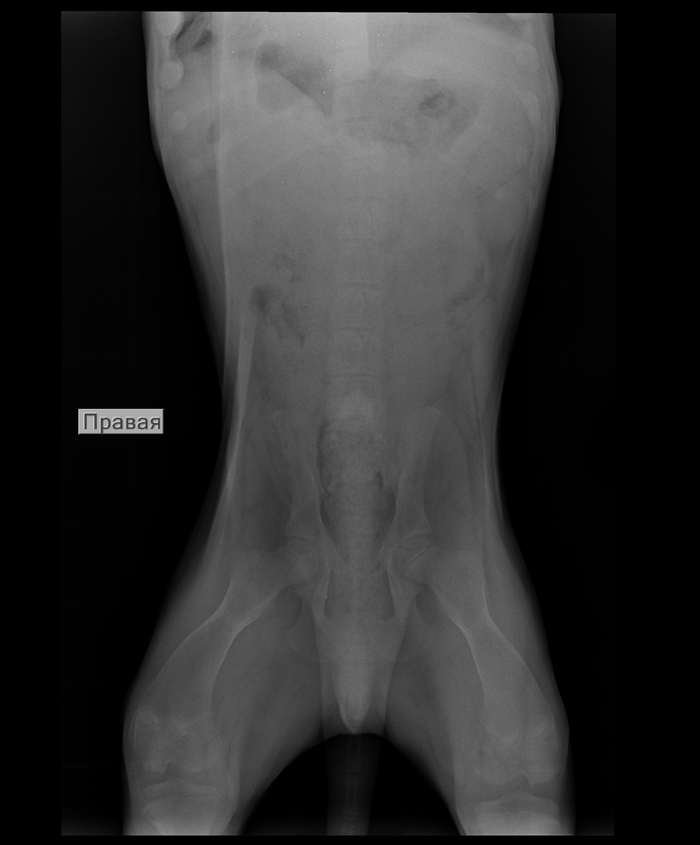

А это собака с переломом позвоночника. Если ей обеспечить должный уход, она будет в режиме счастливой дурилки. Но да, лишь при должном уходе, иначе все обернется смертью от застоя мочи, цистита, почечной недостаточности, ну и дерматиты вдогонку.

А еще я лично знаю как минимум нескольких животных с переломом позвоночника, которым удалось выработать спинальную походку, благодаря стараниям владельцев, и в итоге владельцы просто следят за их мочеиспусканием и дефекацией, помогая опорожнить мочевой пузырь мануально, а животные радуются жизни и радуют владельцев.